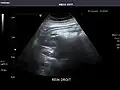

Renal ultrasonography

Ultrasonography of the kidneys is essential in the diagnosis and management of kidney-related diseases. The kidneys are easily examined, and most pathological changes in the kidneys are distinguishable with ultrasound.[7]

Kidneys: Right and left kidneys measure 11.5 cm and 12 cm in length respectively. No hydronephrosis. Small left lower pole kidney cyst.

Right kidney -